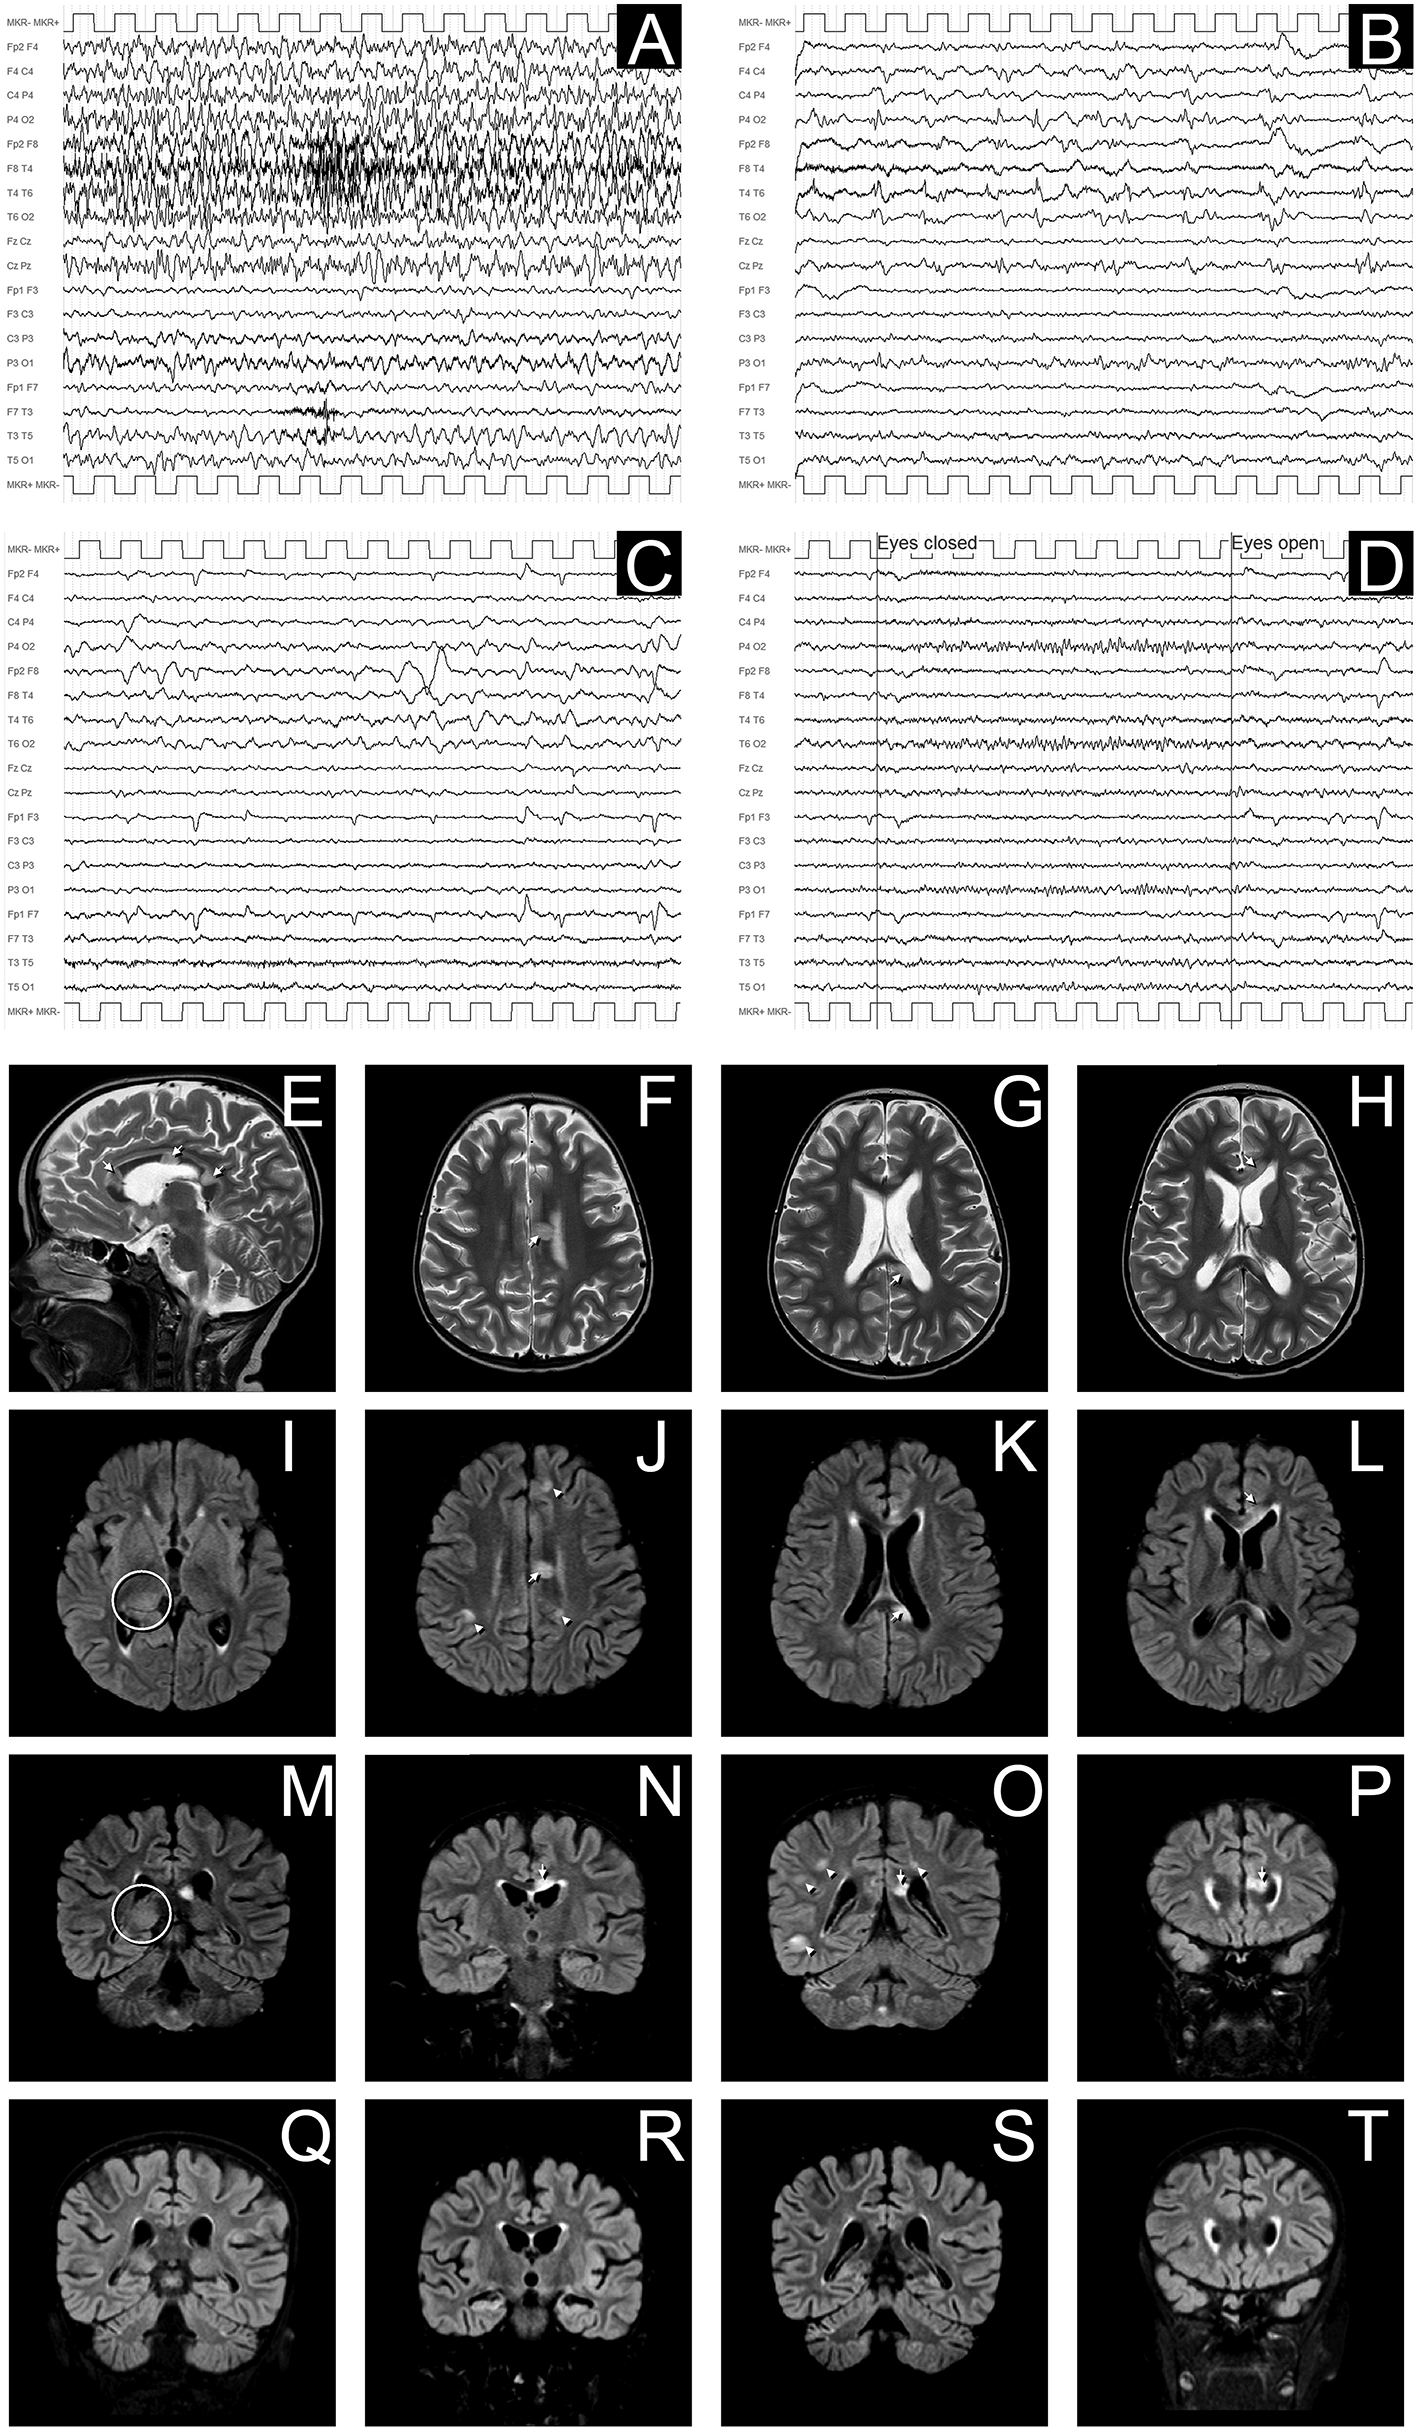

Conditioning regimen was based on treosulfan (3 × 12 g/m2/day), fludarabine (5 × 30 mg/m2/day), thiotepa (2 × 5 mg/kg), and rabbit antithymocyte globulin (ATG NeoviiTM) (3 × 13 mg/kg/day). The composition of the graft was: total nucleated cell (TNC) 5.66 × 108/kg and CD34+ 5.55 × 106/kg. Graft vs. host disease (GVHD) prophylaxis was based on cyclosporine and short term methotrexate. The result of AIRE mutation arrived during the first month of HSCT, confirming that the girl presented the same AIRE mutation as her sister (homozygous mutation in exon 6: c.769C>T (p.Arg257*). Meanwhile, after a transient increase of neutrophil count on day + 19 (peak neutrophil count of 6.920/mm3), the patient presented a progressive decrease of neutrophil count and the chimerism analysis performed on day + 26 confirmed the graft failure (0% donor-derived cells). Given the patient good clinical conditions, a second transplant from the same unrelated donor was scheduled 42 days after the first transplant. Considering the complete bone marrow aplasia, a reduced intensity conditioning regimen, similar to that recommended for severe aplastic anemia, was used: rabbit antithymocyte globulin (ATG GenzymeTM) (3 × 3.3 mg/kg/day), cyclophosphamide (4 × 30 mg/kg/day), fludarabine (4 × 30 mg/ m2/day), while GVHD prophylaxis was based on cyclosporine and short term methotrexate. The graft cell dose was: TNC 5.82 × 108/kg and CD34+ 2.62 × 106/kg. On day +5 the child presented sub-acute onset of headache, lethargy, confusion, slurred speech, and left-hemibody hyposthenia. The electroencephalogram (EEG) showed a continuous ictal epileptic discharge involving the right hemisphere (Figure 2A), consistent with the diagnosis of focal status epilepticus (SE), successfully treated with intravenous administration of levetiracetam and phenytoin. Once SE was controlled, a residual confusional state was observed with EEG, showing an encephalopathic pattern characterized by diffuse slowing clearly predominant on the right hemisphere and periodic temporo-occipital sharp transients (Figure 2B). Brain MRI showed multiple focal hyperintense lesions in T2-weighted (Figures 2E–H) and FLAIR (Figures 2I–P) sequences, localized in corpus callosum (Figures 2E–P), right posterior thalamus (Figures 2I,M) and at the cortico-subcortical junction bilaterally(Figures 2J,O), mainly on the right hemisphere. The cerebrospinal fluid (CSF) findings showed elevated protein concentration while it resulted negative for bacterial and viral infections. Serum and CSF analysis resulted negative for anti-glutamic acid decarboxylase antibodies (anti-GAD), anti-NMDAR, anti-AMPA1, anti-AMPA2, anti-CASPR2, anti-LGI1, anti-GABARB1/B2, anti-myelin oligodendrocyte glycoprotein antibodies (anti-MOG), while the presence of oligoclonal bands was detect only in CSF. The patient was treated with intravenous immunoglobulins (2 g/kg) with gradual clinical improvement in 3 days and complete resolution of symptoms within a week. The EEG performed after 10 days from onset demonstrated a slight inter-hemispheric asymmetry, due to excessive slow activities on the right posterior regions (Figure 2C). A follow-up MRI performed 30 days after the encephalitic episode showed a complete resolution of the focal lesions (Figures 2Q–T). After a primary myeloid engraftment on day +13 (peak neutrophil count of 5.400/mm3), the patient had another early secondary graft failure on day +30 (0% donor-derived cells). Despite that, since day +30 the girl had a progressive recovery of blood values and she no longer needed transfusions, maintaining a normal blood count on erythropoietin treatment. A bone marrow aspirate performed 100 days after the second transplant showed a normal trilineage haematopoiesis with the presence of erythroid precursors (Figure 3), whereas the chimerism confirmed a complete recipient reconstitution (0% donor-derived cells). The EEG performed 3 months after encephalitis showed a complete normalization of previous pathological findings (Figure 2D). At her last follow-up visit on day +150 after the second transplant, the child is in excellent general condition (Lansky play score 100%) with a normal blood count and transfusion-independency although supported with erythropoietin (10,000 UI once every 2 weeks).

Figure 2

EEG and MRI evolution of encephalitic episode. (A–D) EEG recordings in longitudinal bipolar montage, 15 s each panel, calibration (MKR) amplitude 100 μV. In (A) a clear-cut ongoing epileptic discharge involving the right hemisphere (mainly the infrasylvian derivations) is documented, clinically associated with the sub-acute onset of neurological symptoms, consistent with the diagnosis of focal Non-Convulsive Status Epilepticus (NCSE). In (B) the recording obtained 8 h later, after intravenous levetiracetam and phenytoin treatment, shows the resolution of the NCSE with residual diffuse slowing (predominant on the right hemisphere) and periodic temporo-occipital sharp transients (more evident on P4-O2, T4-T6, and T6-O2 channels). Ten days after sub-acute onset, the EEG does not show epileptiform discharges, but an increased amount of slow activity remains, with obvious preponderance on the right temporal regions (C). In (D) the EEG recording performed after 3 months demonstrates a complete recovery, with normal reactivity of the posterior background alpha rhythm. (E–P): Brain MRI images obtained at the onset of neurological symptoms, demonstrating multiple focal hyperintense lesions in T2-weighted (sagittal plane in E; axial images in F–H) and FLAIR (axial images I–L; coronal plane in M–P) sequences. The largest 3 lesions were located in corpus callosum (arrows in E–H,J–L,N–P). A clear hyperintensity was also visible on the right posterior thalamus (circles in I,M). Multiple lesions were evident at the cortico-subcortical junction bilaterally (arrowheads in J,O), mainly involving the right hemisphere, being the largest in the right temporo-occipital region (O). The MRI performed 30 days after the encephalitic episode showed a complete resolution of the focal lesions (in panels Q–T are depicted the correspondent coronal FLAIR images as in M–P).